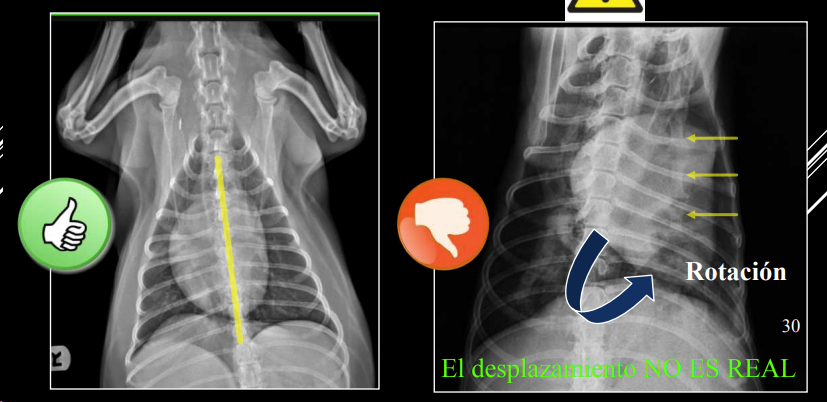

1. Desplazamientos

- Artefacto (rotación): desplazamiento no real. Si se ve el esternon está mal